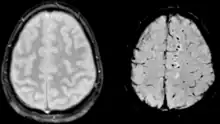

| Two MRI images of a patient with diffuse axonal injury resulting from trauma, at 1.5 tesla field strength. Left: conventional gradient recalled echo (GRE). Right: Susceptibility weighted image (SWI). | |

DAI is difficult to detect since it does not show up well on CT scans or with other macroscopic imaging techniques, though it shows up microscopically.[9] However, there are characteristics typical of DAI that may or may not show up on a CT scan. Diffuse injury has more microscopic injury than macroscopic injury and is difficult to detect with CT and MRI, but its presence can be inferred when small bleeds are visible in the corpus callosum or the cerebral cortex.[34] MRI is more useful than CT for detecting characteristics of diffuse axonal injury in the subacute and chronic time frames.[35] Newer studies such as Diffusion Tensor Imaging are able to demonstrate the degree of white matter fiber tract injury even when the standard MRI is negative. Since axonal damage in DAI is largely a result of secondary biochemical cascades, it has a delayed onset, so a person with DAI who initially appears well may deteriorate later. Thus injury is frequently more severe than is realized, and medical professionals should suspect DAI in any patients whose CT scans appear normal but who have symptoms like unconsciousness.[9]

MRI is more sensitive than CT scans, but is still liable to false negatives because DAI is identified by looking for signs of edema, which may not always be present.[33]